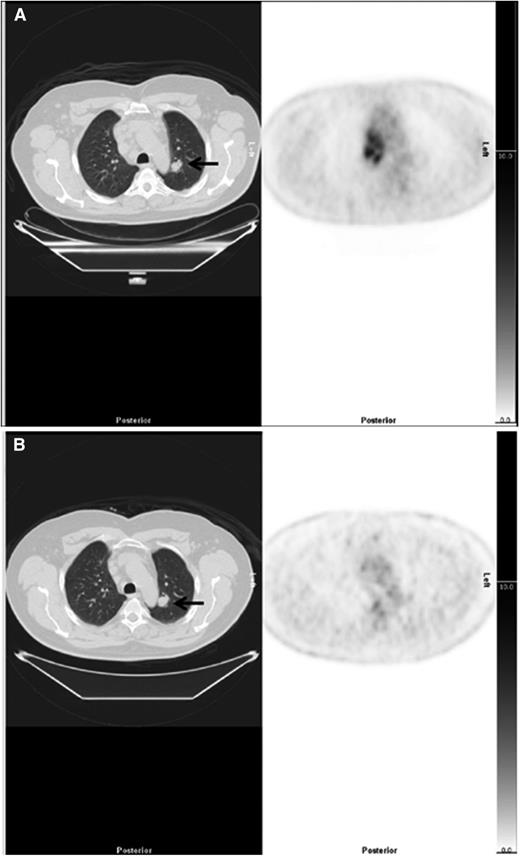

Example of downstaging by PET-CT. (Left) CT and (right) PET axial images show a case downstaged by PET-CT. (A) There was nodal disease in the mediastinum and a 22-mm lung nodule in the left lung (arrow), reported on CT as stage 4. The PET scan showed high uptake in lymph nodes but no FDG uptake in the lung nodule, suggesting the nodule was unlikely to be due to lymphoma interpreted as stage 2. (B) After treatment, there was resolution of uptake in lymph nodes but the lung nodule (arrow) was unchanged.